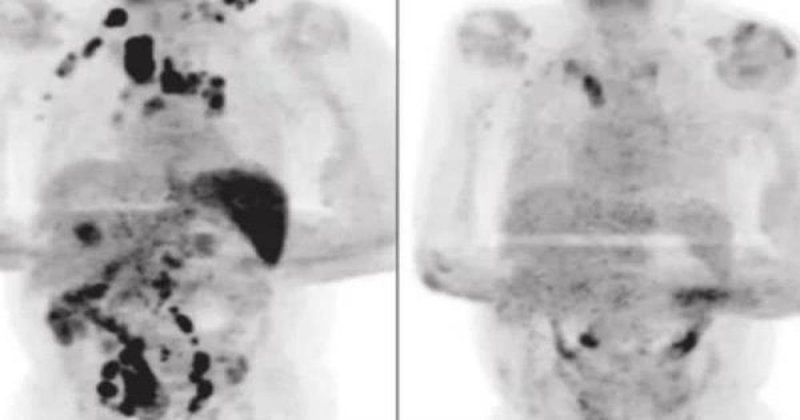

La pandemia del Covid-19 ha dejado muchos duelos en el mundo; sin embargo, a los expertos ha sorprendido un raro caso en específico, pues una persona con linfoma de Hodgkin se curó debido al nuevo coronavirus.

Este caso médico, publicado en el British Journal of Haemathology, pudo superar este tipo de cáncer pese a estar en fase 3 y tener todos los pronósticos en contra, pues su salud estaba deteriorada a sus 61 años.

Los expertos destacaron que durante ese tiempo no se le administró ningún corticosteroide ni alguna inmunoquimioterapia, por lo que al pasar cuatro meses, se sorprendieron al ver que el linforma se habí reducido considerablemente.

La hipótesis de los expertos es que la infección del Covid-19 desencadenó una respuesta inmunitaria antitumoral.